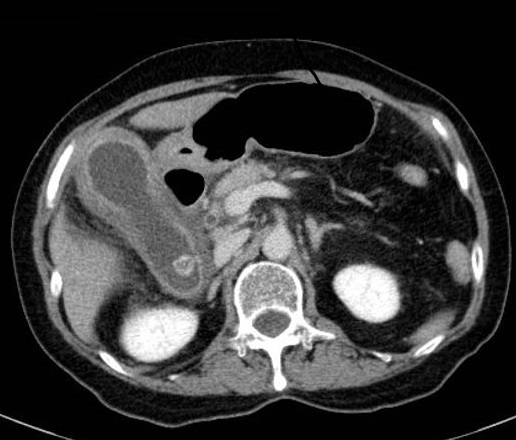

Cholecystite

lithiasique aigue : Vesicule biliaire est distendue

, image epaissisement et rehaussement hyperdense de la paroi

avec epanchement perivesiculaire . La lithiase

hyperdense situe a infundibulum . Image

radiologique TDM + contrast en coupe axiale |

|

Image radiologique TDM

, contrast intraveineuse en coupe coronal : Se

presente une cholecystite aigue avec deux

calculs de la vesicule biliaire . Sa paroi est

epais , oedeme |